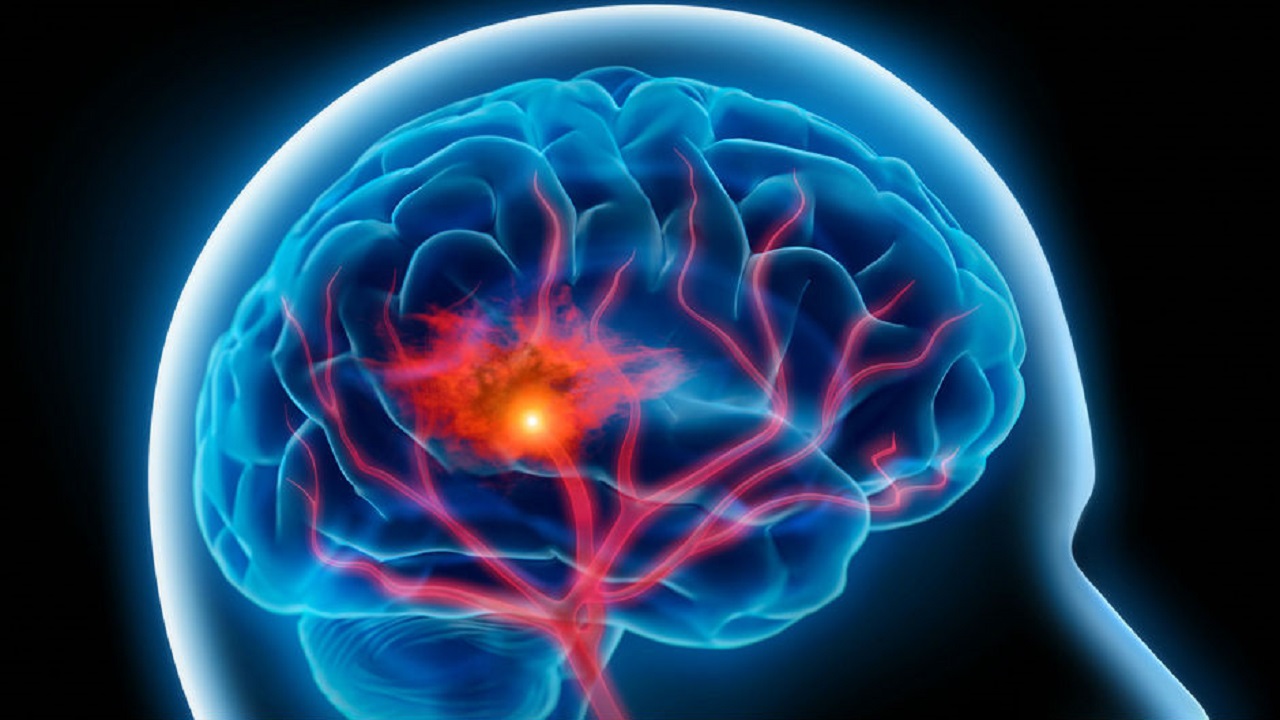

Мождани удар

Мождани удар (у народу познато као шлог) је једно од најтежих обољења које може задесити човека. Долази изненада, оставља последице, често у виду инвалидитета и често мења живот из корена не само оболелом, већ и његовој породици. АЛИ, оно што је охрабрујуће јесте чињеница да се у многим случајевима мождани удар може спречити.